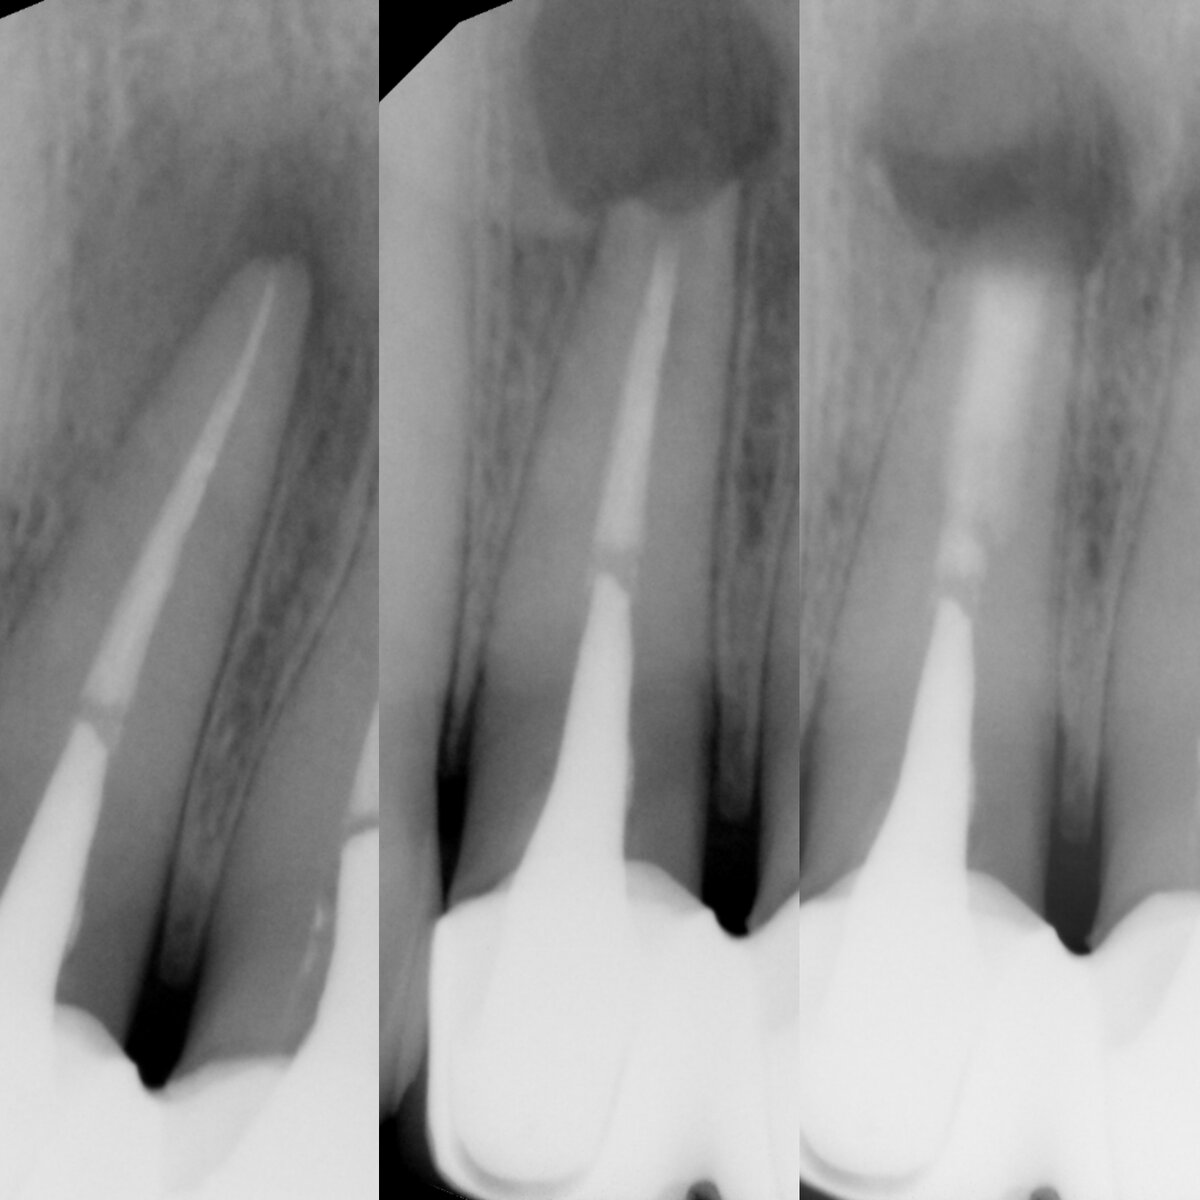

Спустя несколько лет после лечения можно случайно обнаружить очаг воспаления на контрольных снимках и встанет вопрос о повторном лечении под МИКРОСКОПОМ или УДАЛЕНИИ. Но так как задача врача – сохранение зуба, не всегда стоит сразу удалять зуб. Последний шанс для зуба – апикальная микрохирургия.

Апикальная хирургия представляет собой микрооперацию - резекцию верхней четверти/трети корня.

Вместе с корнем удаляется воспалительный очаг, а его место заполняется костной тканью.

Для проведения данных манипуляций используют операционный микроскоп, ультразвуковое и микрохирургическое оборудование, позволяющие провести ретроградное пломбирование минеральным цементом МТП и устранить последствия периодонтита.